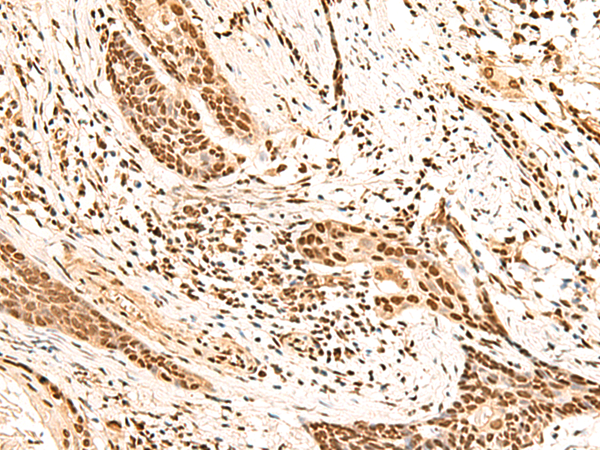

IHC (Immunohistochemistry)

(Immunohistochemistry of paraffin-embedded Human esophagus cancer tissue using HOXC13 Polyclonal Antibody at dilution of 1:60(×200))